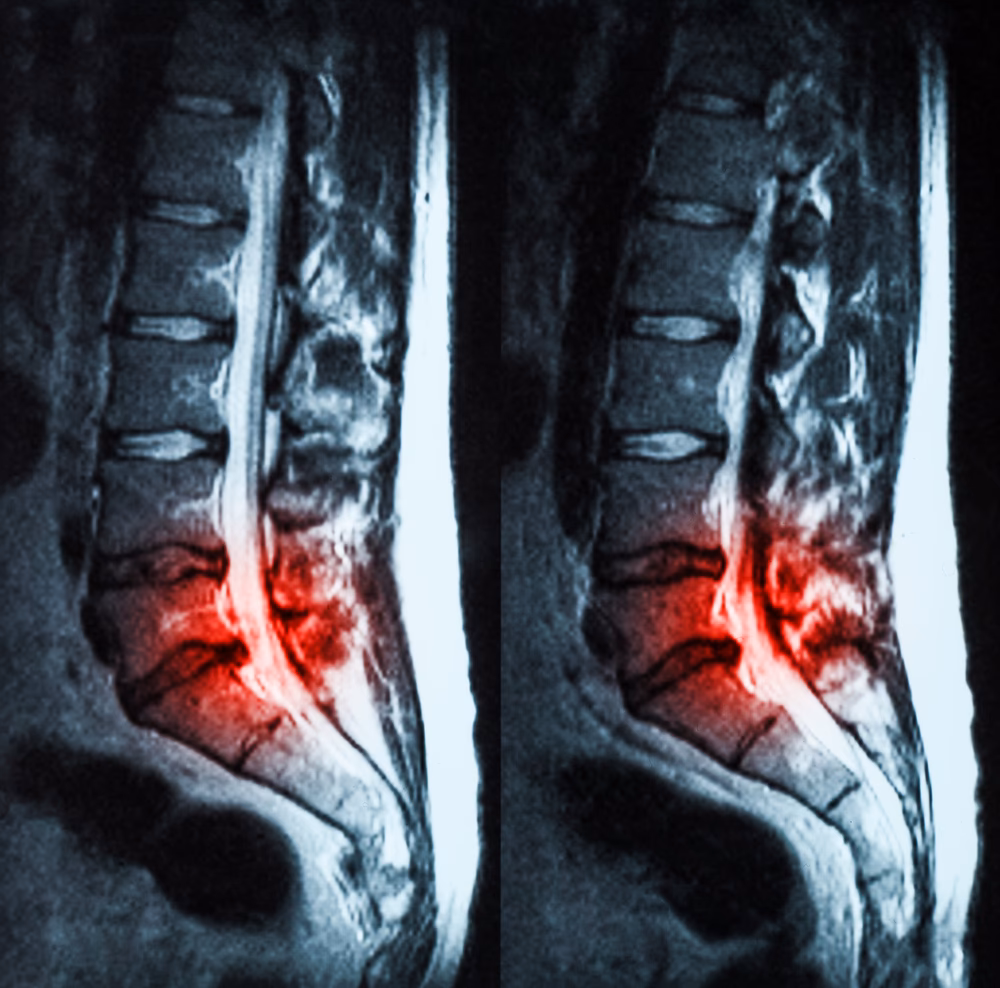

2. Billeddiagnostik: For at få et detaljeret billede af rygsøjlens tilstand kan lægen bestille billeddiagnostiske undersøgelser.

- MR- eller CT-scanninger giver et meget mere detaljeret billede af bløddele som brusk, nerver, diskusskiver og eventuelle cyster.